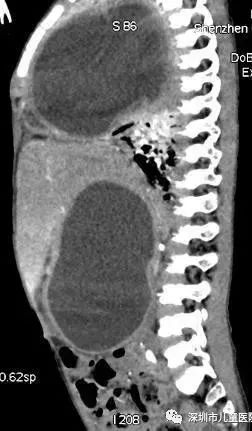

检查结果,让医生倒吸了一口凉气:京京右侧胸腔及右侧腹腔,各有一个巨型囊肿。

手术前,京京胸腹部CT侧面

两处黑色包块状阴影分别为胸腔、腹腔囊肿

图源:深圳市儿童医院

这就像,在他的肚子里塞进了两个“大气球”。正是由于“气球”压迫了肺部,他才会呼吸困难,随时都会有生命危险。